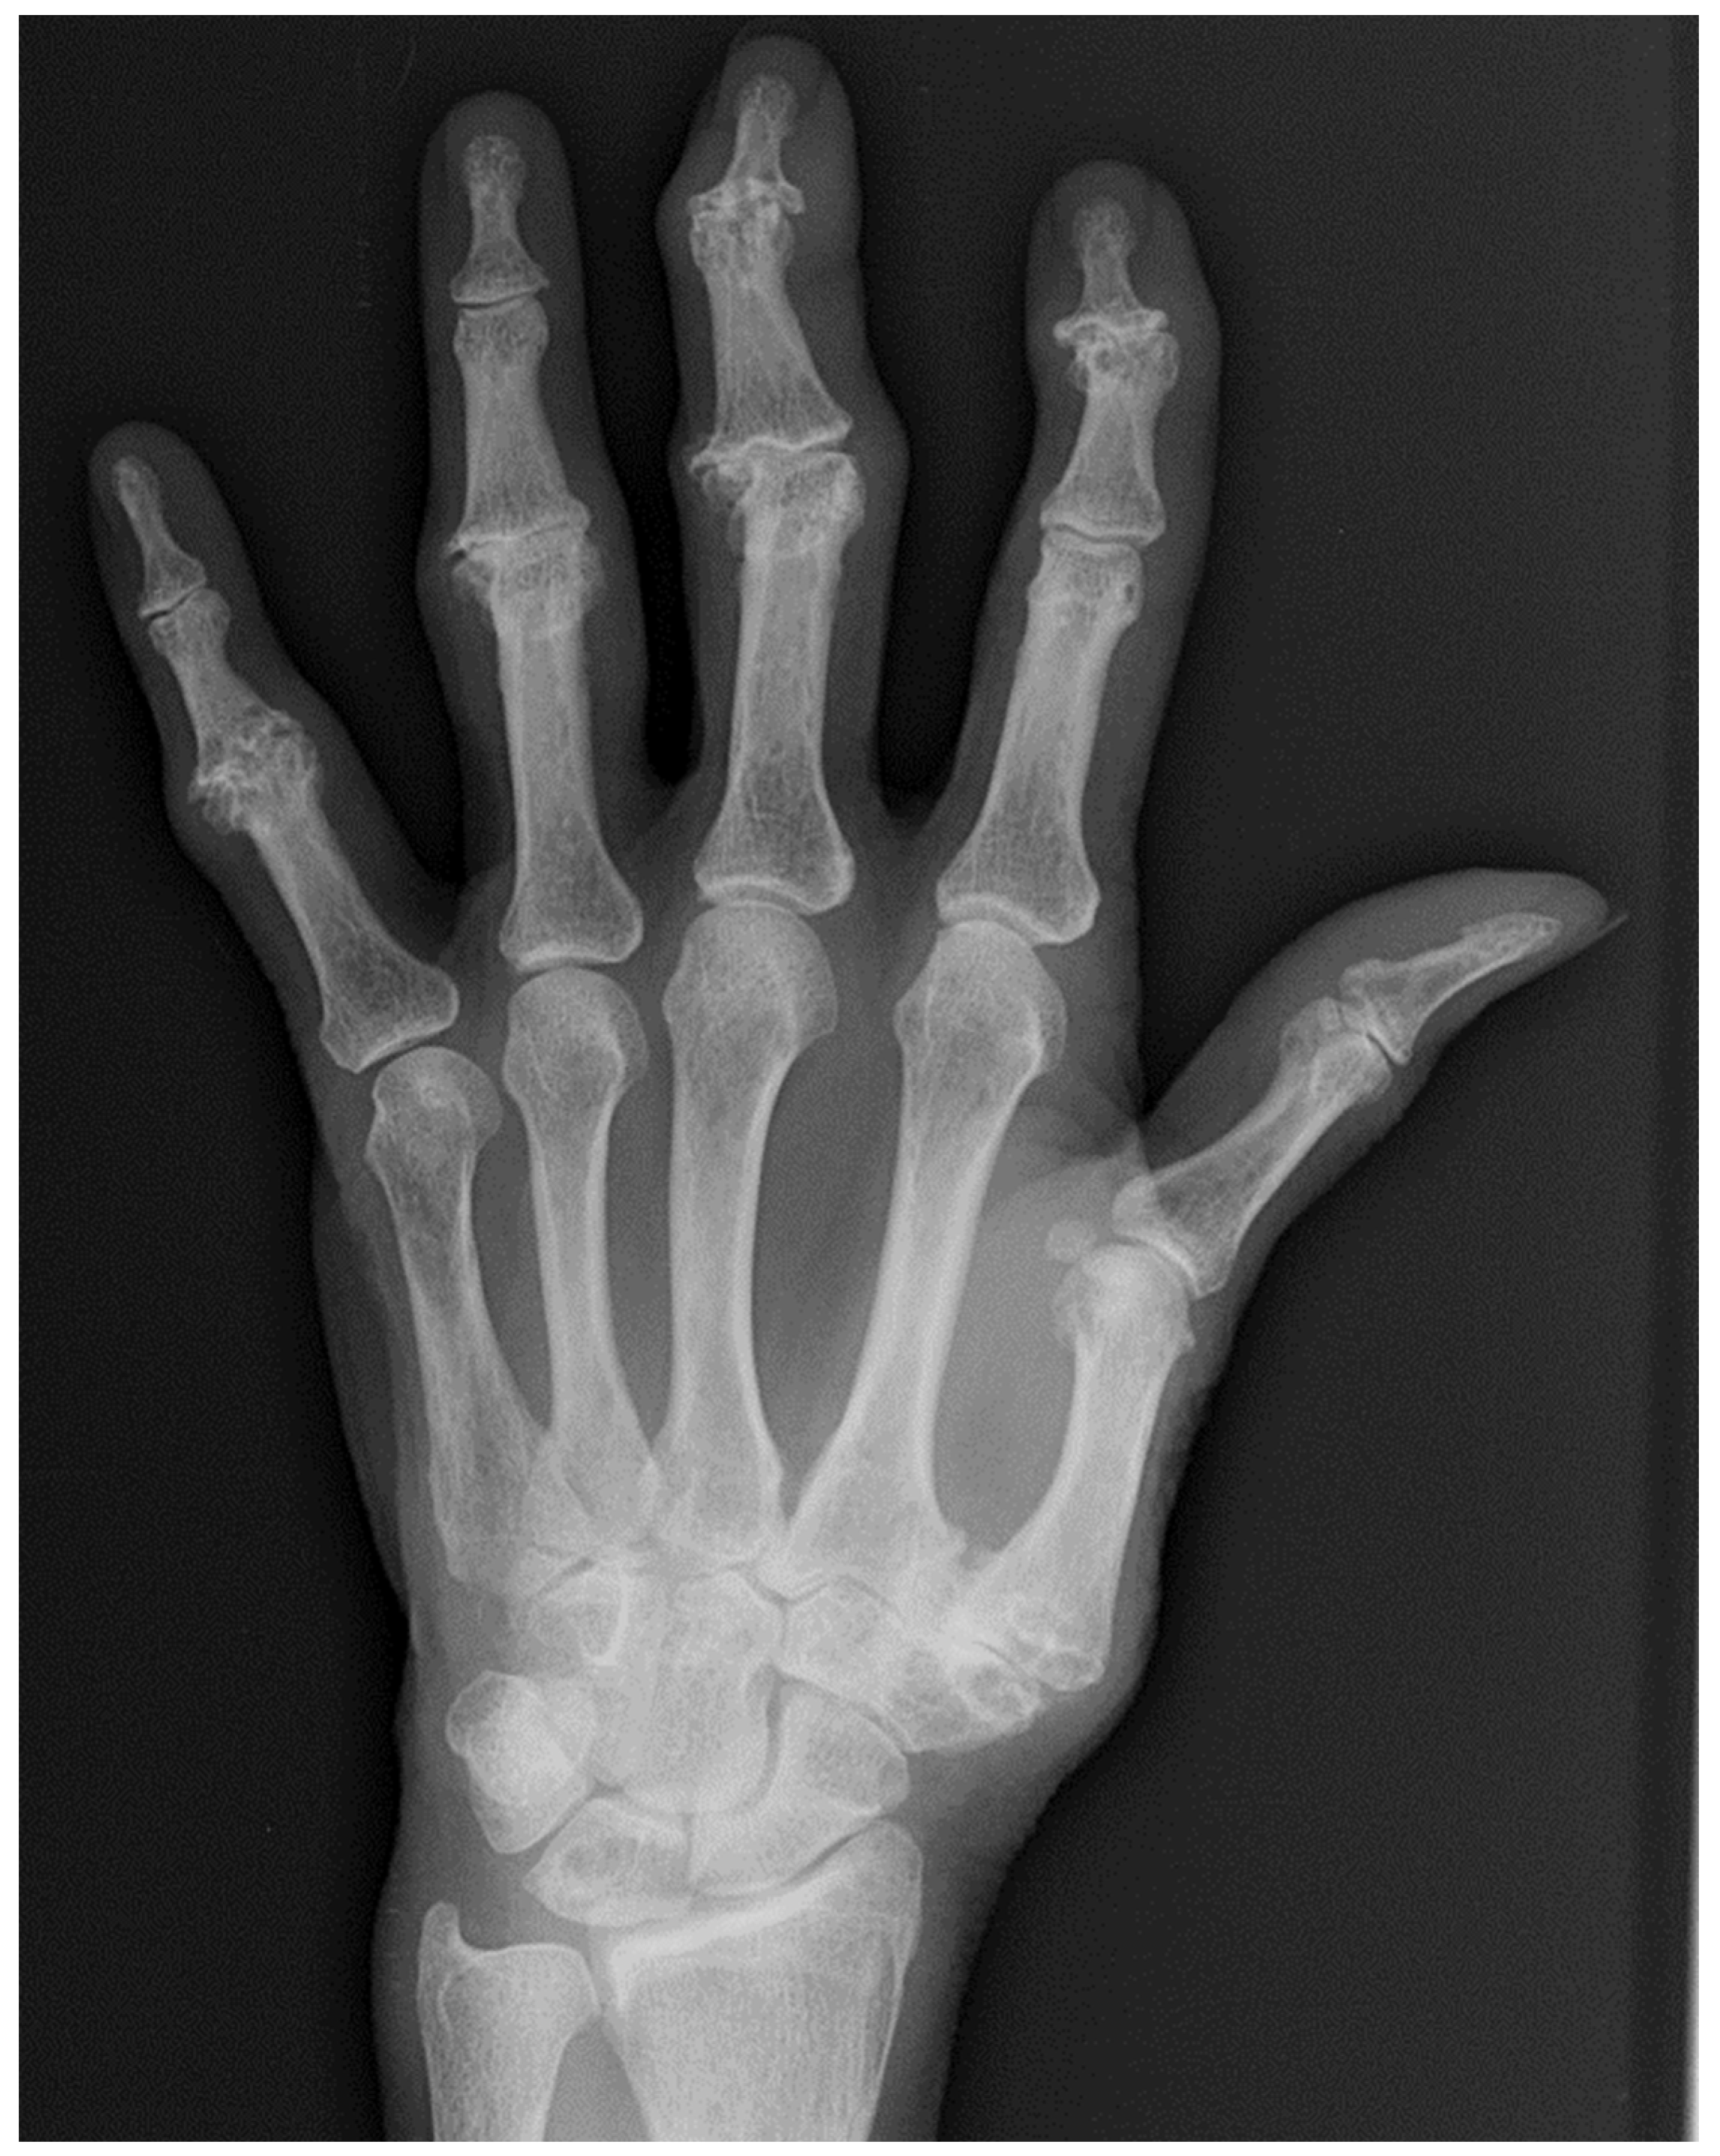

10. Osteoarthritis (OA)